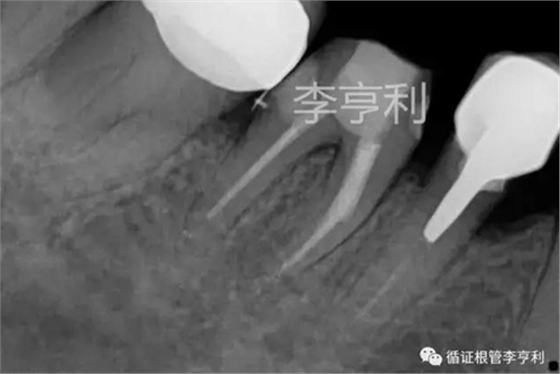

試尖片 (2017-07-03)

術(shù)后片 (2017-07-03)